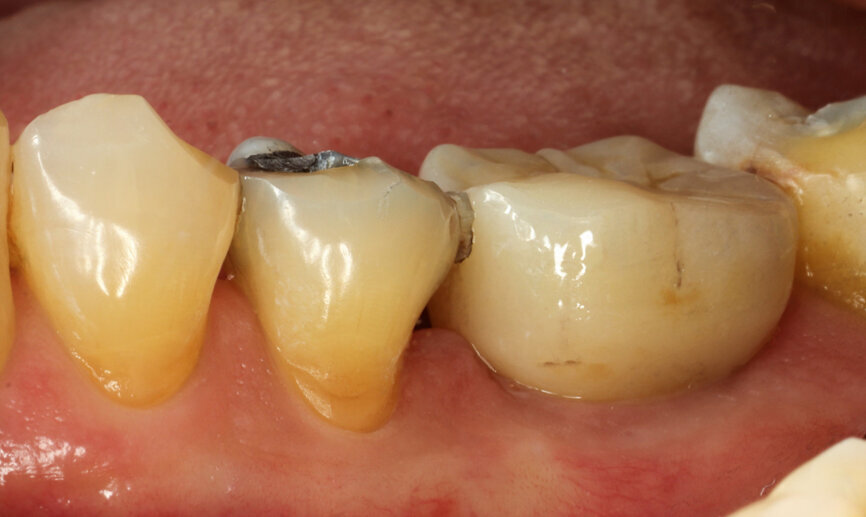

Fig. 21: Gingival healing ready for initiation of definitive crown.

Upon the patient’s return, the definitive crown placement was initiated by another intra-oral scan to copy all the gingival contours after healing (Figs. 21 & 22). A full monolithic zirconia crown was milled and cemented to a Variobase abutment (diameter: 5 mm; height: 6 mm) and properly seated, occlusal and contact points checked. The screw access hole was properly closed with PTFE tape and light-polymerised composite (Fig. 23).

From a clinical perspective, the immediate placement and function were very well indicated as they could be verified through the gingival margins and health, and bone levels throughout the healing phase, and final and one-year follow-up images (Figs. 24–29).